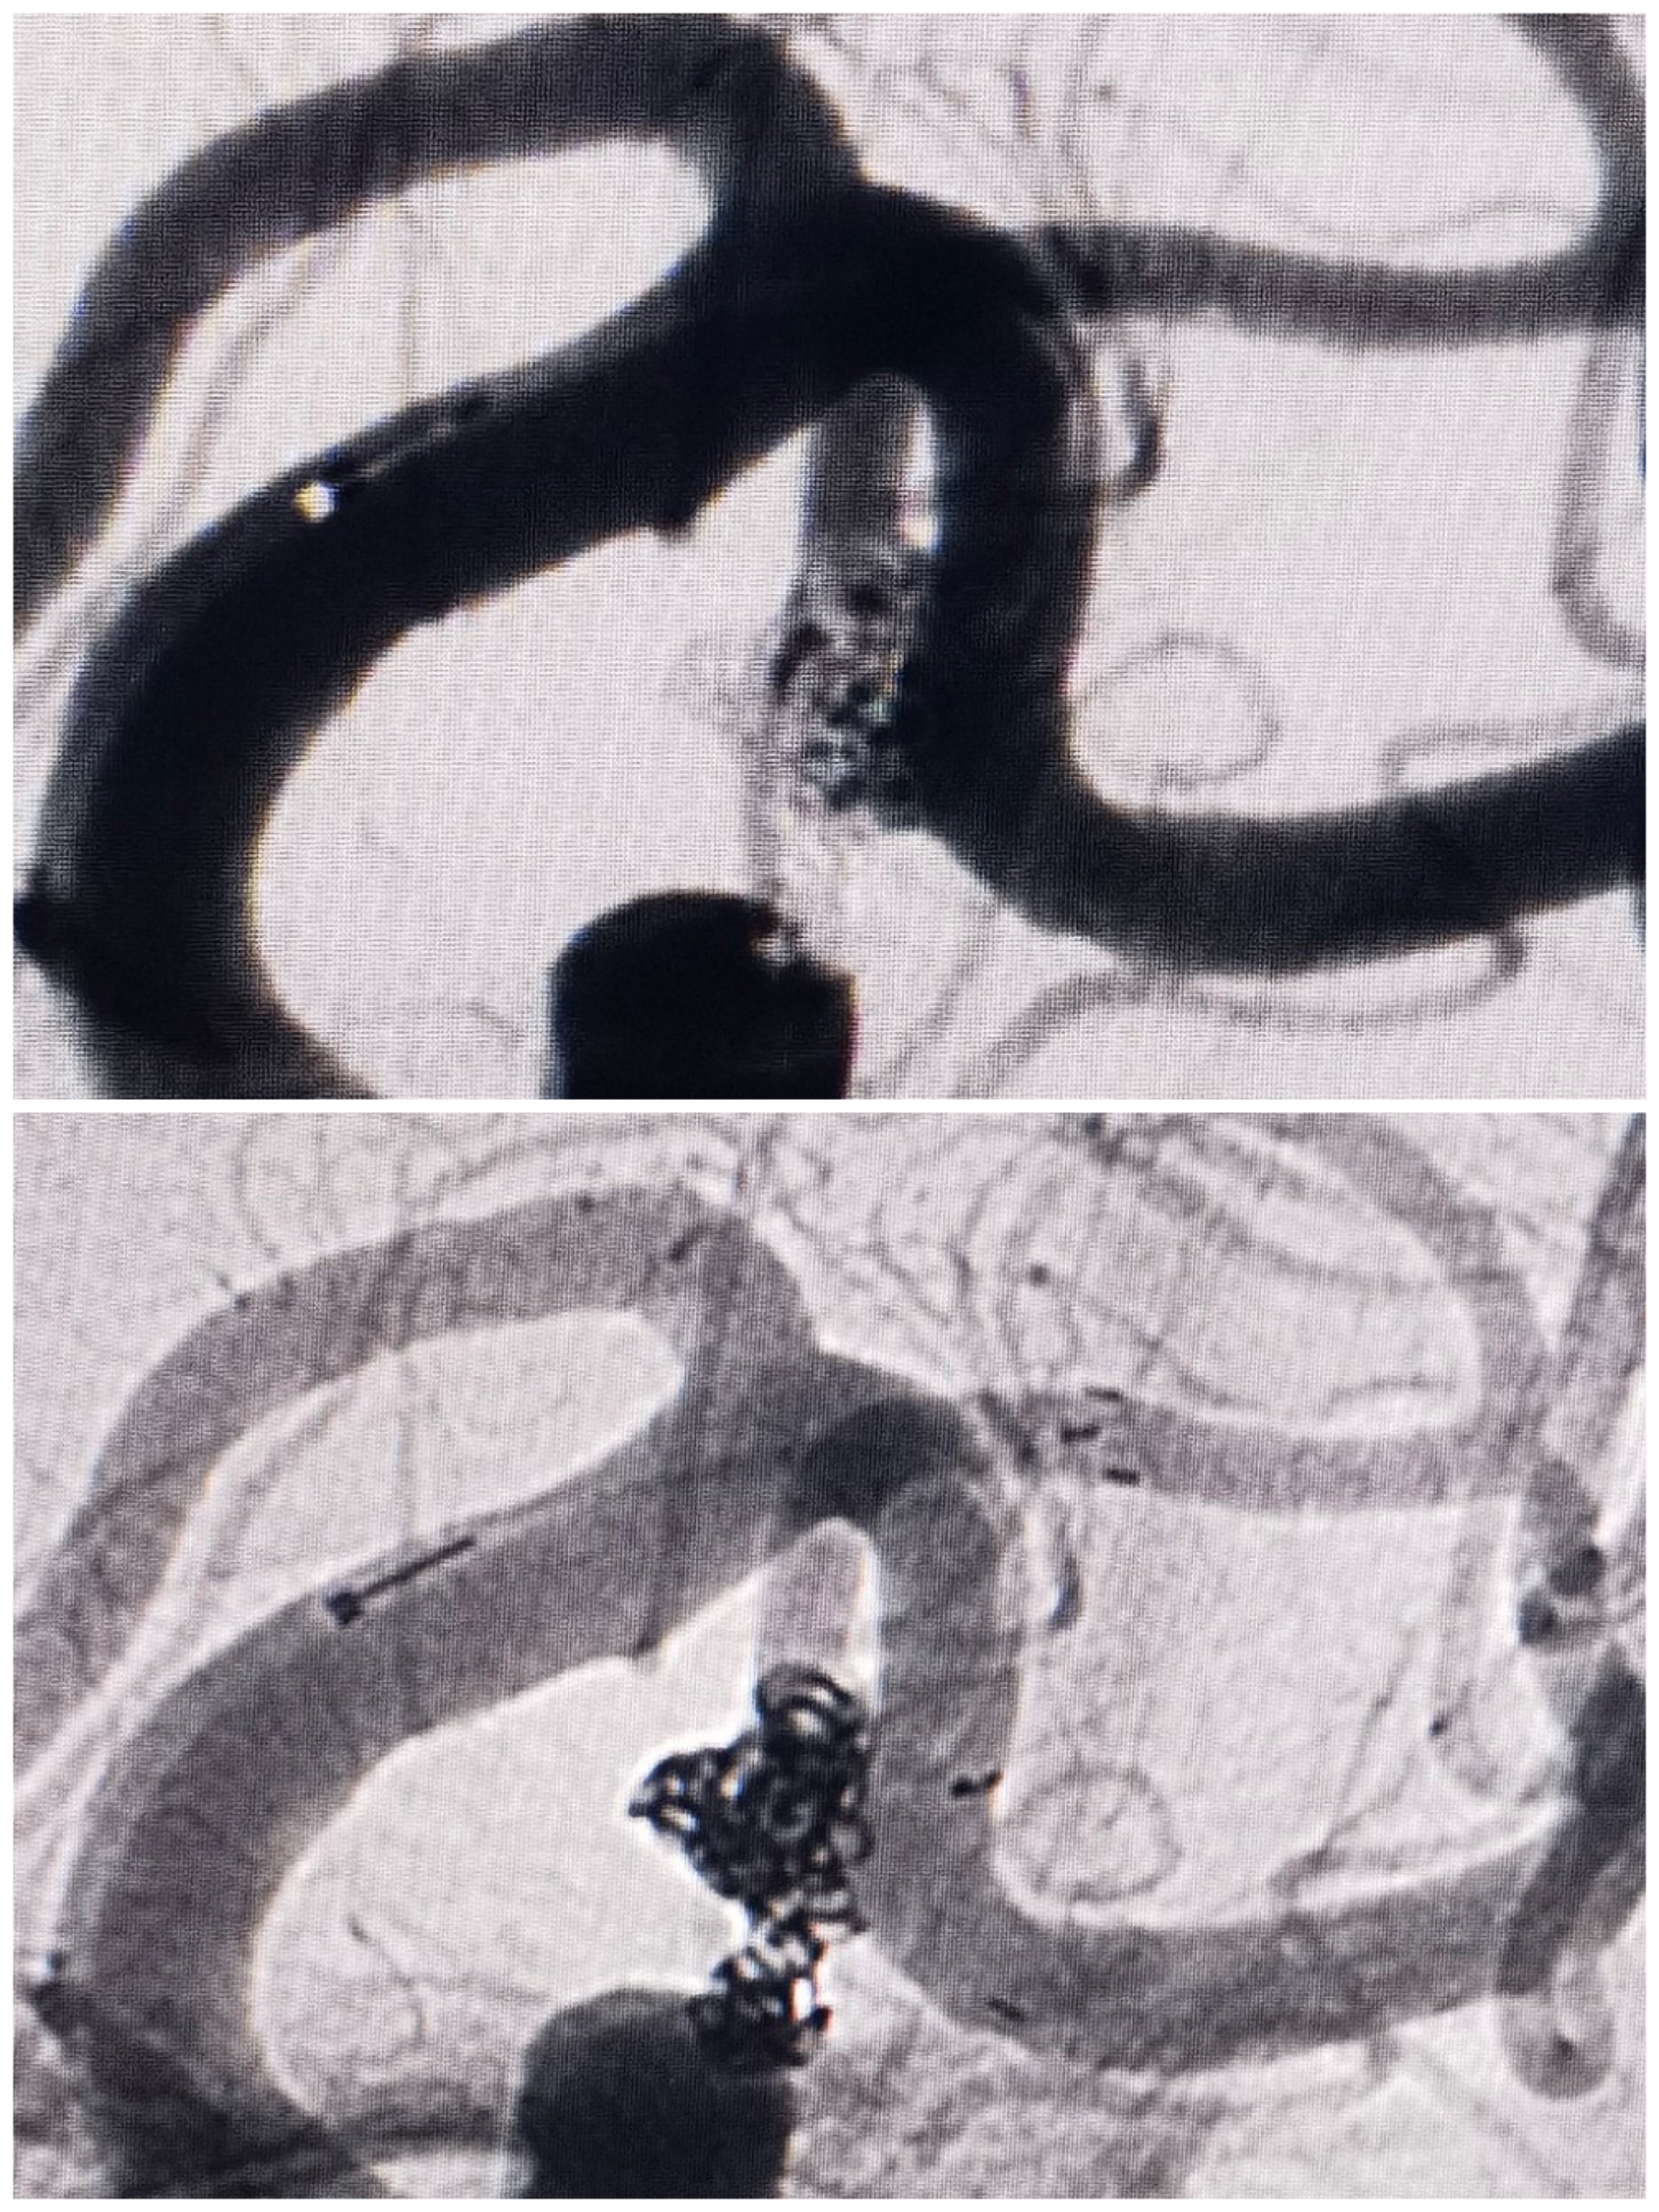

术前造影

3D重建情况

手术过程微导管布局情况:三系统栓塞,支架导管置于上干,两条微导管分别置于主囊和子囊中。

手术过程:先栓塞子囊,释放Atlas支架后甩尾(头端置于上干、尾端甩尾释放于下干开口保护两个干),后栓塞主囊

栓塞术后情况:支架甩尾保护双干,子囊及主囊栓塞完全

术后工作位造影

术后3D旋转

术后3D重建